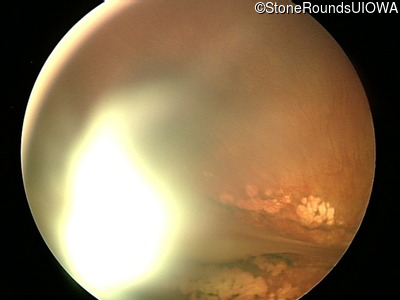

Fundus Photography - Right - 20/400

Exemplar